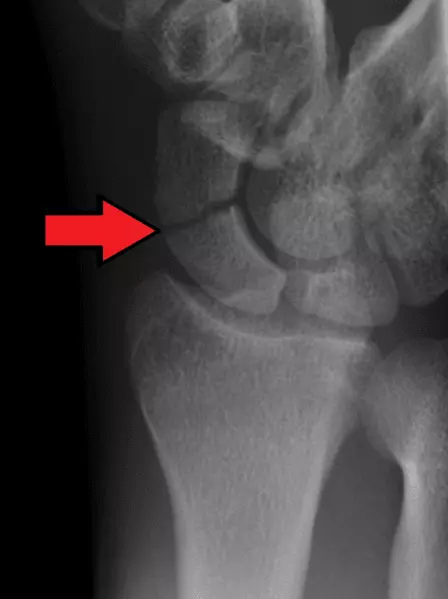

Scaphoid fractures account for 70-80% of all carpal bone fractures. They are caused by a fall onto an outstretched hand (FOOSH) and are most common in young adults.

A scaphoid fracture presents with pain in the anatomical snuffbox (a region just below the base of the thumb) that is exacerbated by movement. Complications include a high risk of non-union and avascular necrosis due to the scaphoid bone having a retrograde blood supply (meaning if there is a fracture that disrupts blood supply, the bone may not heal).

The fracture may not show on the initial X-Ray, but the patient should be treated as if a fracture is present. Then a repeat X-ray may be done 10-14 days later, as the fracture can become visible due to bone resorption along the fracture line, although early MRI or CT is often used to confirm the diagnosis. Treatment may or may not require surgery but a splint or cast is used to increase chances of union of the bone fragments.

Image - An X-Ray showing a scaphoid fracture. The red arrow shows the fracture line